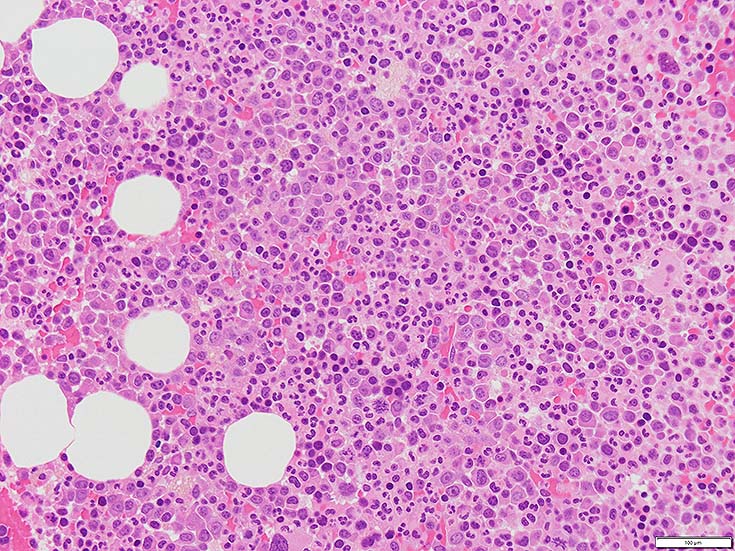

初診時の骨髄組織所見

thumb nail画像のクリックで大きな画像がみられます.

BM-f-01HE01.jpg BM-f-01HE02.jpg BM-f-01.jpg

HE染色および, Naphtol-ASD-CAE染色した骨髄クロット組織標本-->Naphtol-ASD-CAE染色, 載せガラス法のページをみる.

70-80%のhypercellular marrow. 3系統造血細胞が認められる. Naphtol-ASD-CAE染色で赤色にそまる顆粒球系細胞増生が顕著な骨髄組織.

promyelocytesなど幼若顆粒球系細胞の集簇がみられるが, 分葉好中球他, 成熟顆粒球(Naphtol-ASD-CAE染色は薄く染まる傾向あり)も多く認められacute leukaemiaの所見ではない.

単球(Naphtol-ASD-CAE染色陰性)が密に増殖する所見は骨髄組織には認められない(*1)